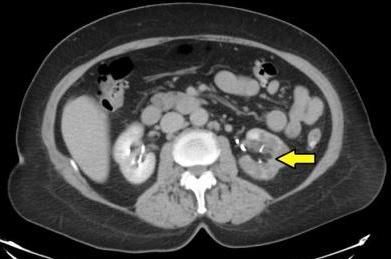

Initial laboratory studies were notable for a serum creatinine level of 1.21 mg/dL. Her serum creatinine value in 2001 was 0.7 mg/dL. Cardiac enzymes were negative for acute coronary syndrome. Aspartate aminotransferase (AST) and alanine aminotransferase (ALT) levels were 57 U/L and 53 U/L, respectively. Urinalysis was unremarkable and negative for hematuria. Blood and urine cultures revealed no growth. ECG in the ED showed normal sinus rhythm without any evidence of acute coronary syndrome. A contrast-enhanced CT scan of the abdomen obtained in the ED showed inhomogeneous uptake of contrast in the left kidney (Figure 1). CT also revealed diffuse diverticulosis of the descending and transverse colon without evidence of diverticulitis.

Figure 1 -

Contrast-enhanced CT of the abdomen showing decreased uptake of contrast in the left kidney.